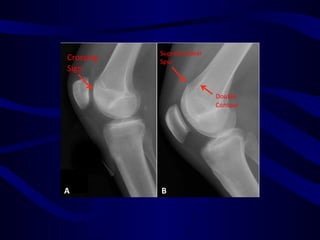

1. X-Ray : Merchant view

1. X-Ray : Sunrise view